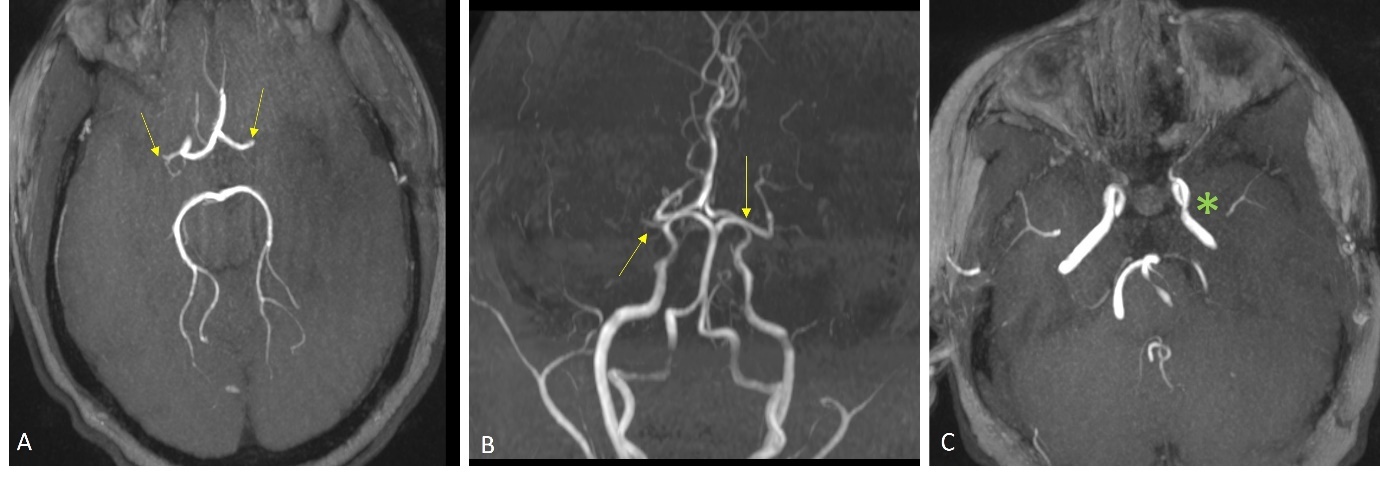

A 13-year-old girl presented with sudden onset of expressive aphasia and right hemiplegia. Her past medical history included type 1 diabetes mellitus on insulin pump therapy and hypertension treated with lisinopril. Her mother had insulin-dependent diabetes mellitus. Her National Institutes of Health Stroke Scale on arrival was 23/30. Computed tomography of the head showed a hypodensity area in the left parietal lobe. The onset of symptoms was outside the time window for intravenous thrombolysis. Magnetic resonance imaging (MRI) imaging revealed subacute infarct in the left middle cerebral artery (MCA) distribution and bilateral chronic lacunar infarcts. Magnetic resonance angiography (MRA) demonstrated bilateral MCA M1 occlusions (Figure 1), suggestive of Moyamoya disease.

There were no collateral vessels and the bilateral supra-clinoid internal carotid arteries (ICAs) were relatively spared. Perfusion imaging showed a mismatched diffusion-positive defect, and a normal perfusion pattern for the occluded right M1 segment of MCA. MRI imaging of the vessel wall was performed. It showed minimal enhancement of the proximal left M1 segment and sluggish blood flow in the distal MCA, findings which favored Moyamoya disease and pointed against intracranial atherosclerotic disease. She underwent catheter angiography- which showed complete occlusion of the right M1 segment at the ICA termination and robust leptomeningeal collateral derived from the right anterior cerebral artery. (Figure 2)